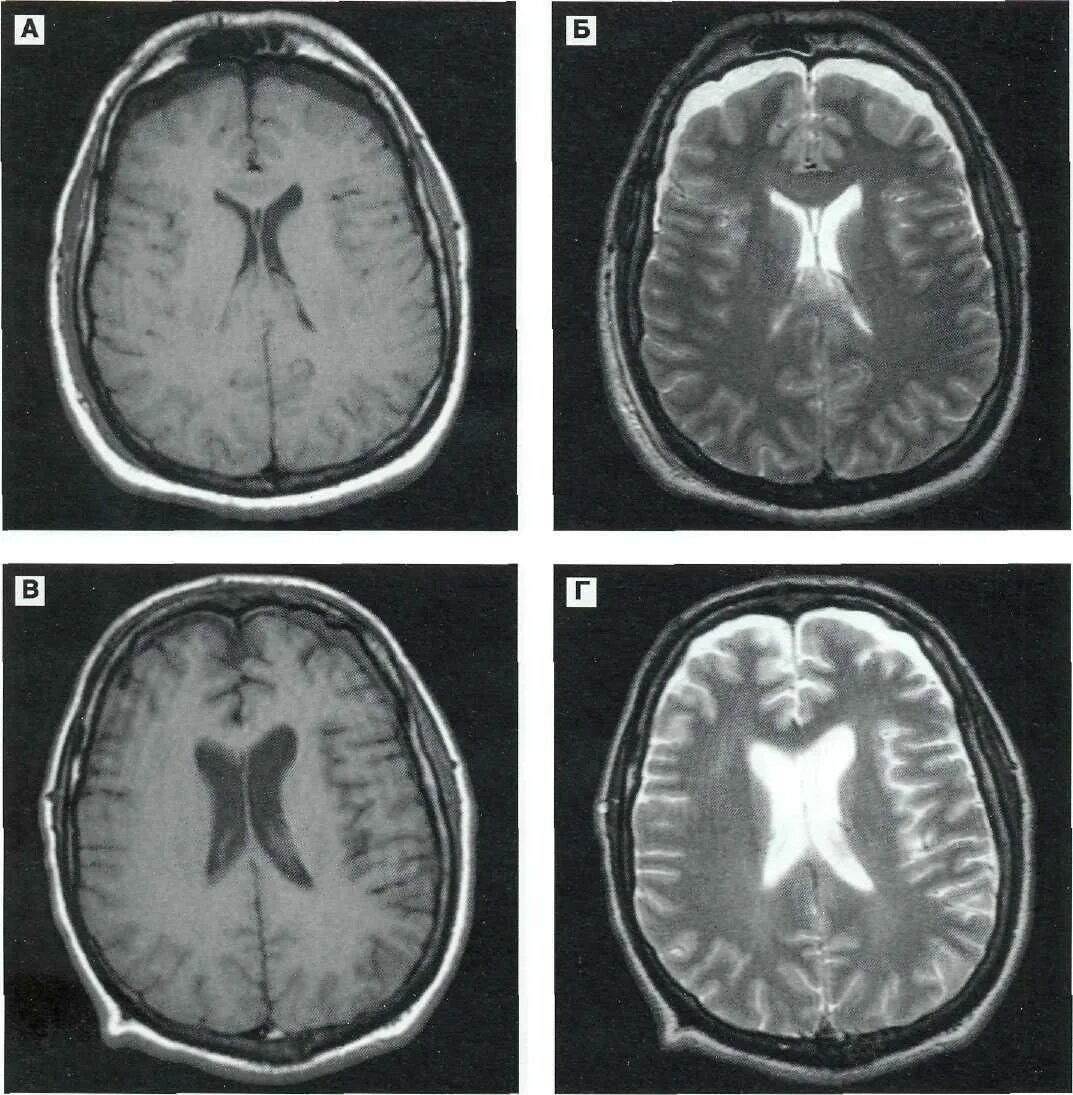

Диффузное поражение головного